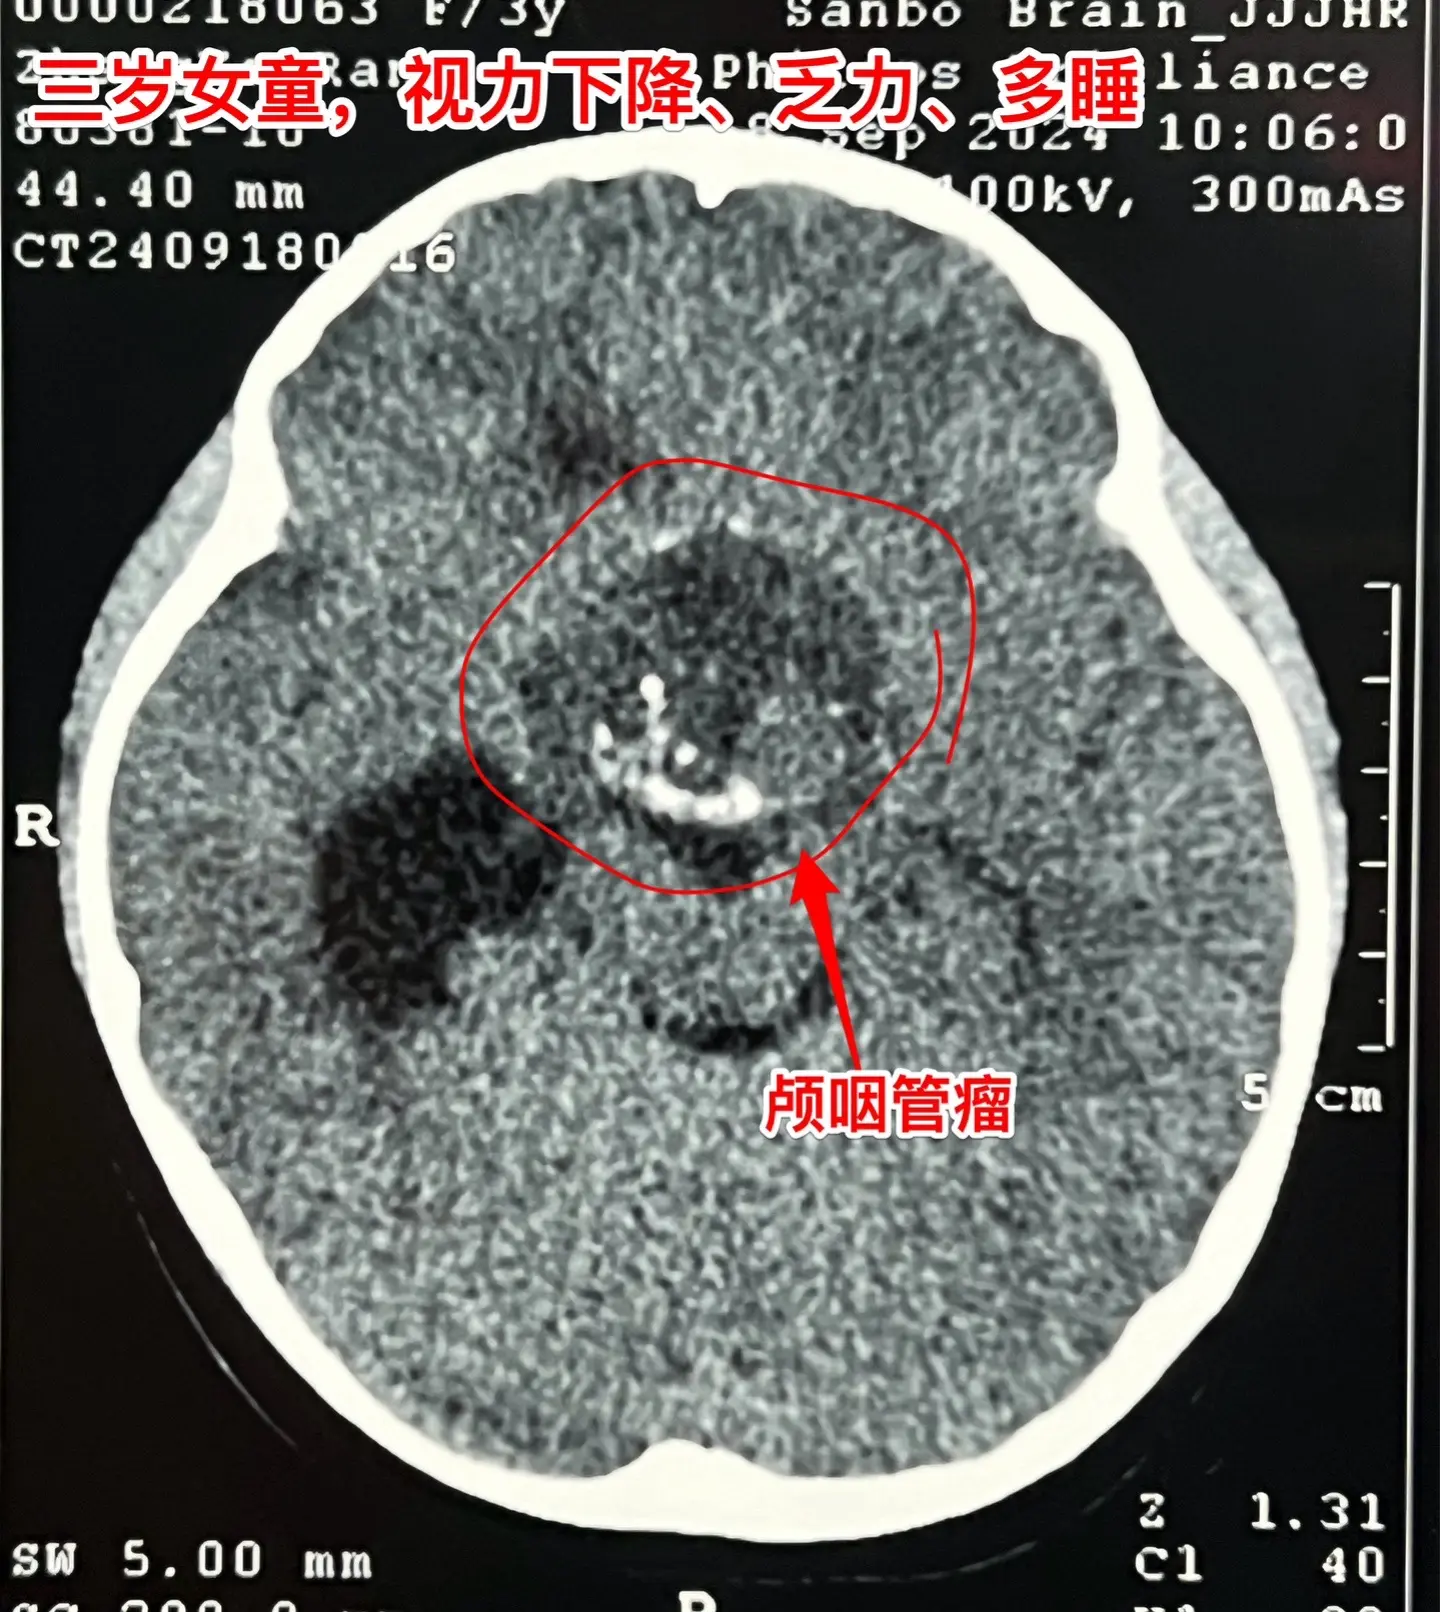

商丘市女娃患颅咽管瘤。3岁女娃,商丘市的。近一个月视力下降,家长发现她爱用左眼看东西,不用右眼看。而且娃娃还乏力,没精神,爱睡觉睡。到医院检查出的结果让父母难以面对:脑部居然长了一个6厘米大的颅咽管瘤。 中秋节放假期间一家人没有心思在家过中秋节,急匆匆地到三博脑科医院神经外科八病区住院。 9月24日作了开颅手术,顺利切除颅咽管瘤。 女娃昨天晚上就从ICU转回了普通病房。 昨日商丘居然下大雨、涨大水了! 但愿一切安好!